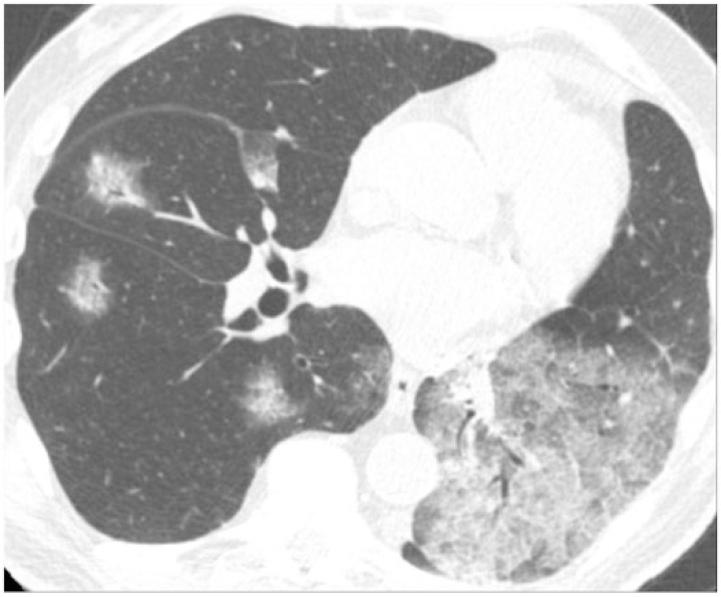

Pulmonary nodules, both solid and subsolid, are common incidental findings on computed tomography (CT) studies. Subsolid nodules (SSNs) may be further classified as either pure ground-glass nodules or part-solid nodules. The differential diagnosis for an SSN is broad, including infection, organizing pneumonia, inflammation, hemorrhage, focal fibrosis, and neoplasm. Adenocarcinomas of the lung are currently the most common type of lung cancer, representing 30-35% of all primary lung tumors, and the subtype of bronchioloalveolar cell carcinoma (BAC) commonly presents as an SSN. In 2011, a new classification system for lung adenocarcinomas was proposed by the International Association for the Study of Lung Cancer, the American Thoracic Society, and the European Respiratory Society. An important feature of the new system is the relinquishment of the term BAC in favor of more specific histologic subtypes. It has been reported that these subtypes are associated with characteristic CT findings. This article reviews the new classification system of lung adenocarcinomas, discusses and illustrates the associated CT findings, and outlines the current recommendations for further diagnosis, treatment, and follow-up of SSNs based on computed tomography findings.

肺部结节,无论是实性还是亚实性,都是计算机断层扫描(CT)研究中的常见偶然发现。亚实性结节(SSN)可进一步分为纯磨玻璃结节或部分实性结节。SSN 的鉴别诊断范围很广,包括感染、机化性肺炎、炎症、出血、局灶性纤维化和肿瘤。肺腺癌是目前最常见的肺癌类型,占所有原发性肺肿瘤的 30-35%,而细支气管肺泡细胞癌(BAC)亚型通常表现为 SSN。2011 年,国际肺癌研究协会、美国胸科学会和欧洲呼吸学会提出了一种新的肺腺癌分类系统。该系统的一个重要特点是放弃 BAC 一词,转而采用更具特异性的组织学亚型。据报道,这些亚型与特征性 CT 表现有关。本文回顾了肺腺癌的新分类系统,讨论并说明了相关的 CT 发现,并概述了基于 CT 发现对 SSN 进行进一步诊断、治疗和随访的当前建议。